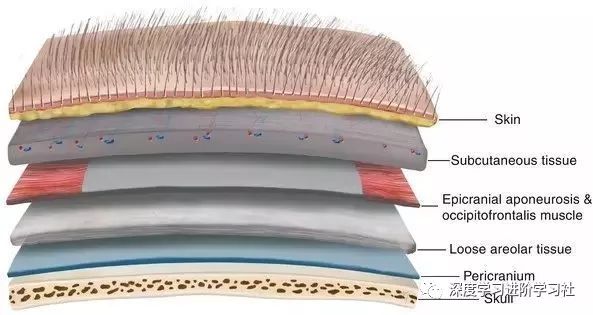

你有头发,然后是头皮,你认为下面就是你的头骨了——但实际上头骨之上还有19样东西。

你的头骨下面,又是一大堆东西,之后才是你的大脑:

从左到右是皮肤(粉红色),然后是两个头皮层,然后是头骨,然后是硬脑膜,蛛网膜,最右边是只由软脑膜覆盖的大脑。